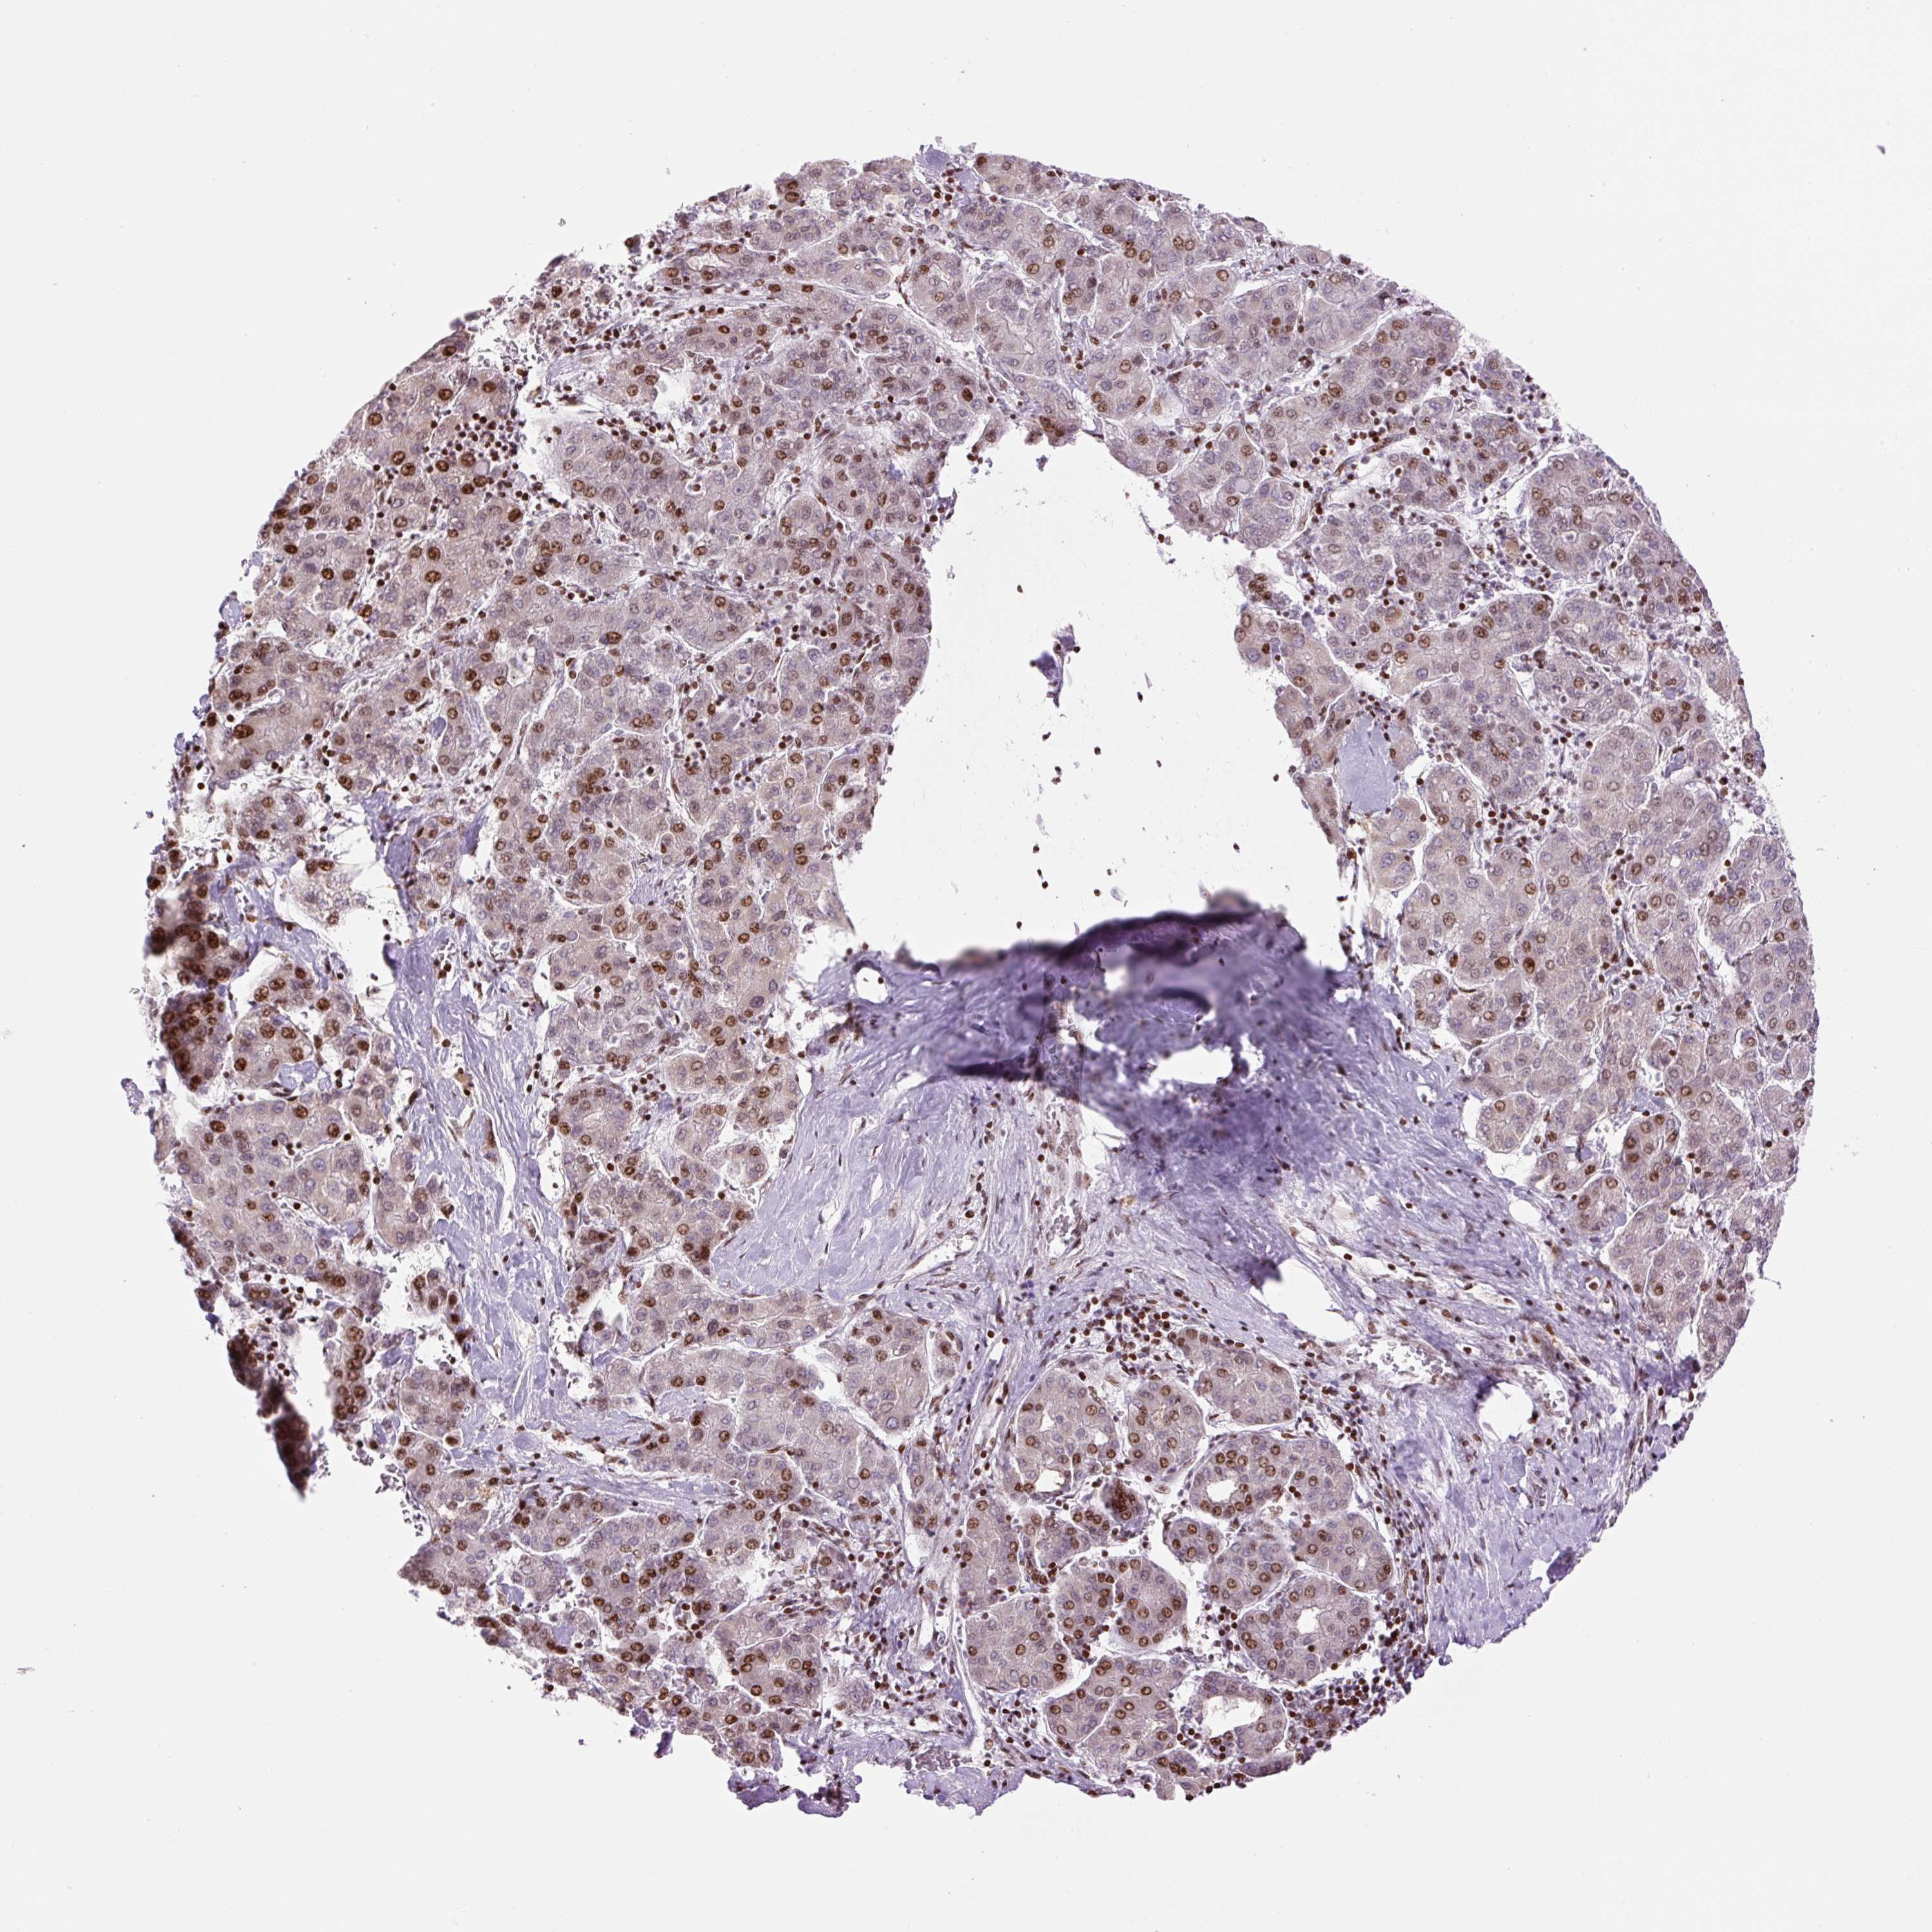

LIVER CANCER - Protein expressioni

A mouse-over function shows sample information and annotation data. Click on an image to view it in a full screen mode. Samples can be filtered based on level of antibody staining by selecting one or several of the following categories: high, medium, low and not detected. The assay and annotation is described here.

Note that samples used for immunohistochemistry by the Human Protein Atlas do not correspond to samples in the TCGA dataset.

Antibody stainingi

Antibody staining in the annotated cell types in the current human tissue is reported as not detected, low, medium, or high, based on conventional immunohistochemistry profiling in selected tissues. This score is based on the combination of the staining intensity and fraction of stained cells.

Each image is clickable and will lead to virtual microscopy that enables deeper exploration of all samples and also displays staining intensity scores, fraction scores and subcellular localization as well as patient and tissue information for each sample.

Antibody HPA053816

Staining

High

Medium

Low

Not detected

Intensity

Strong

Moderate

Weak

Negative

Quantity

>75%

75%-25%

<25%

None

Location

Nuclear

Cytoplasmic/membranous

Cytoplasmic/membranous,nuclear

Carcinoma, Hepatocellular, NOS

Cholangiocarcinoma